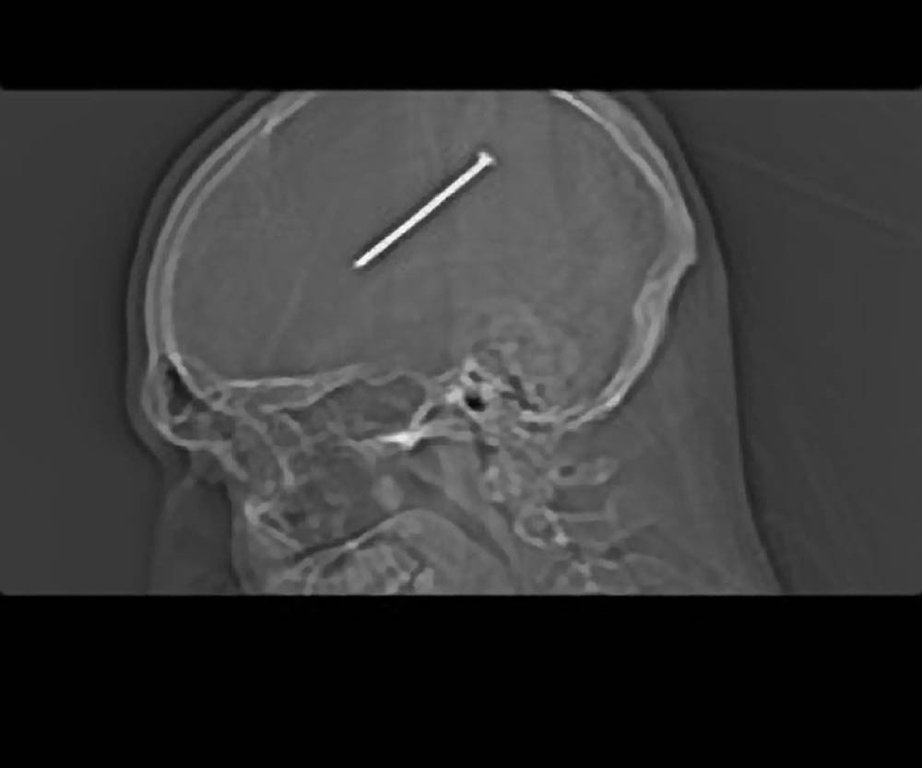

Nagel ins Hirn geschossen und nichts gemerkt